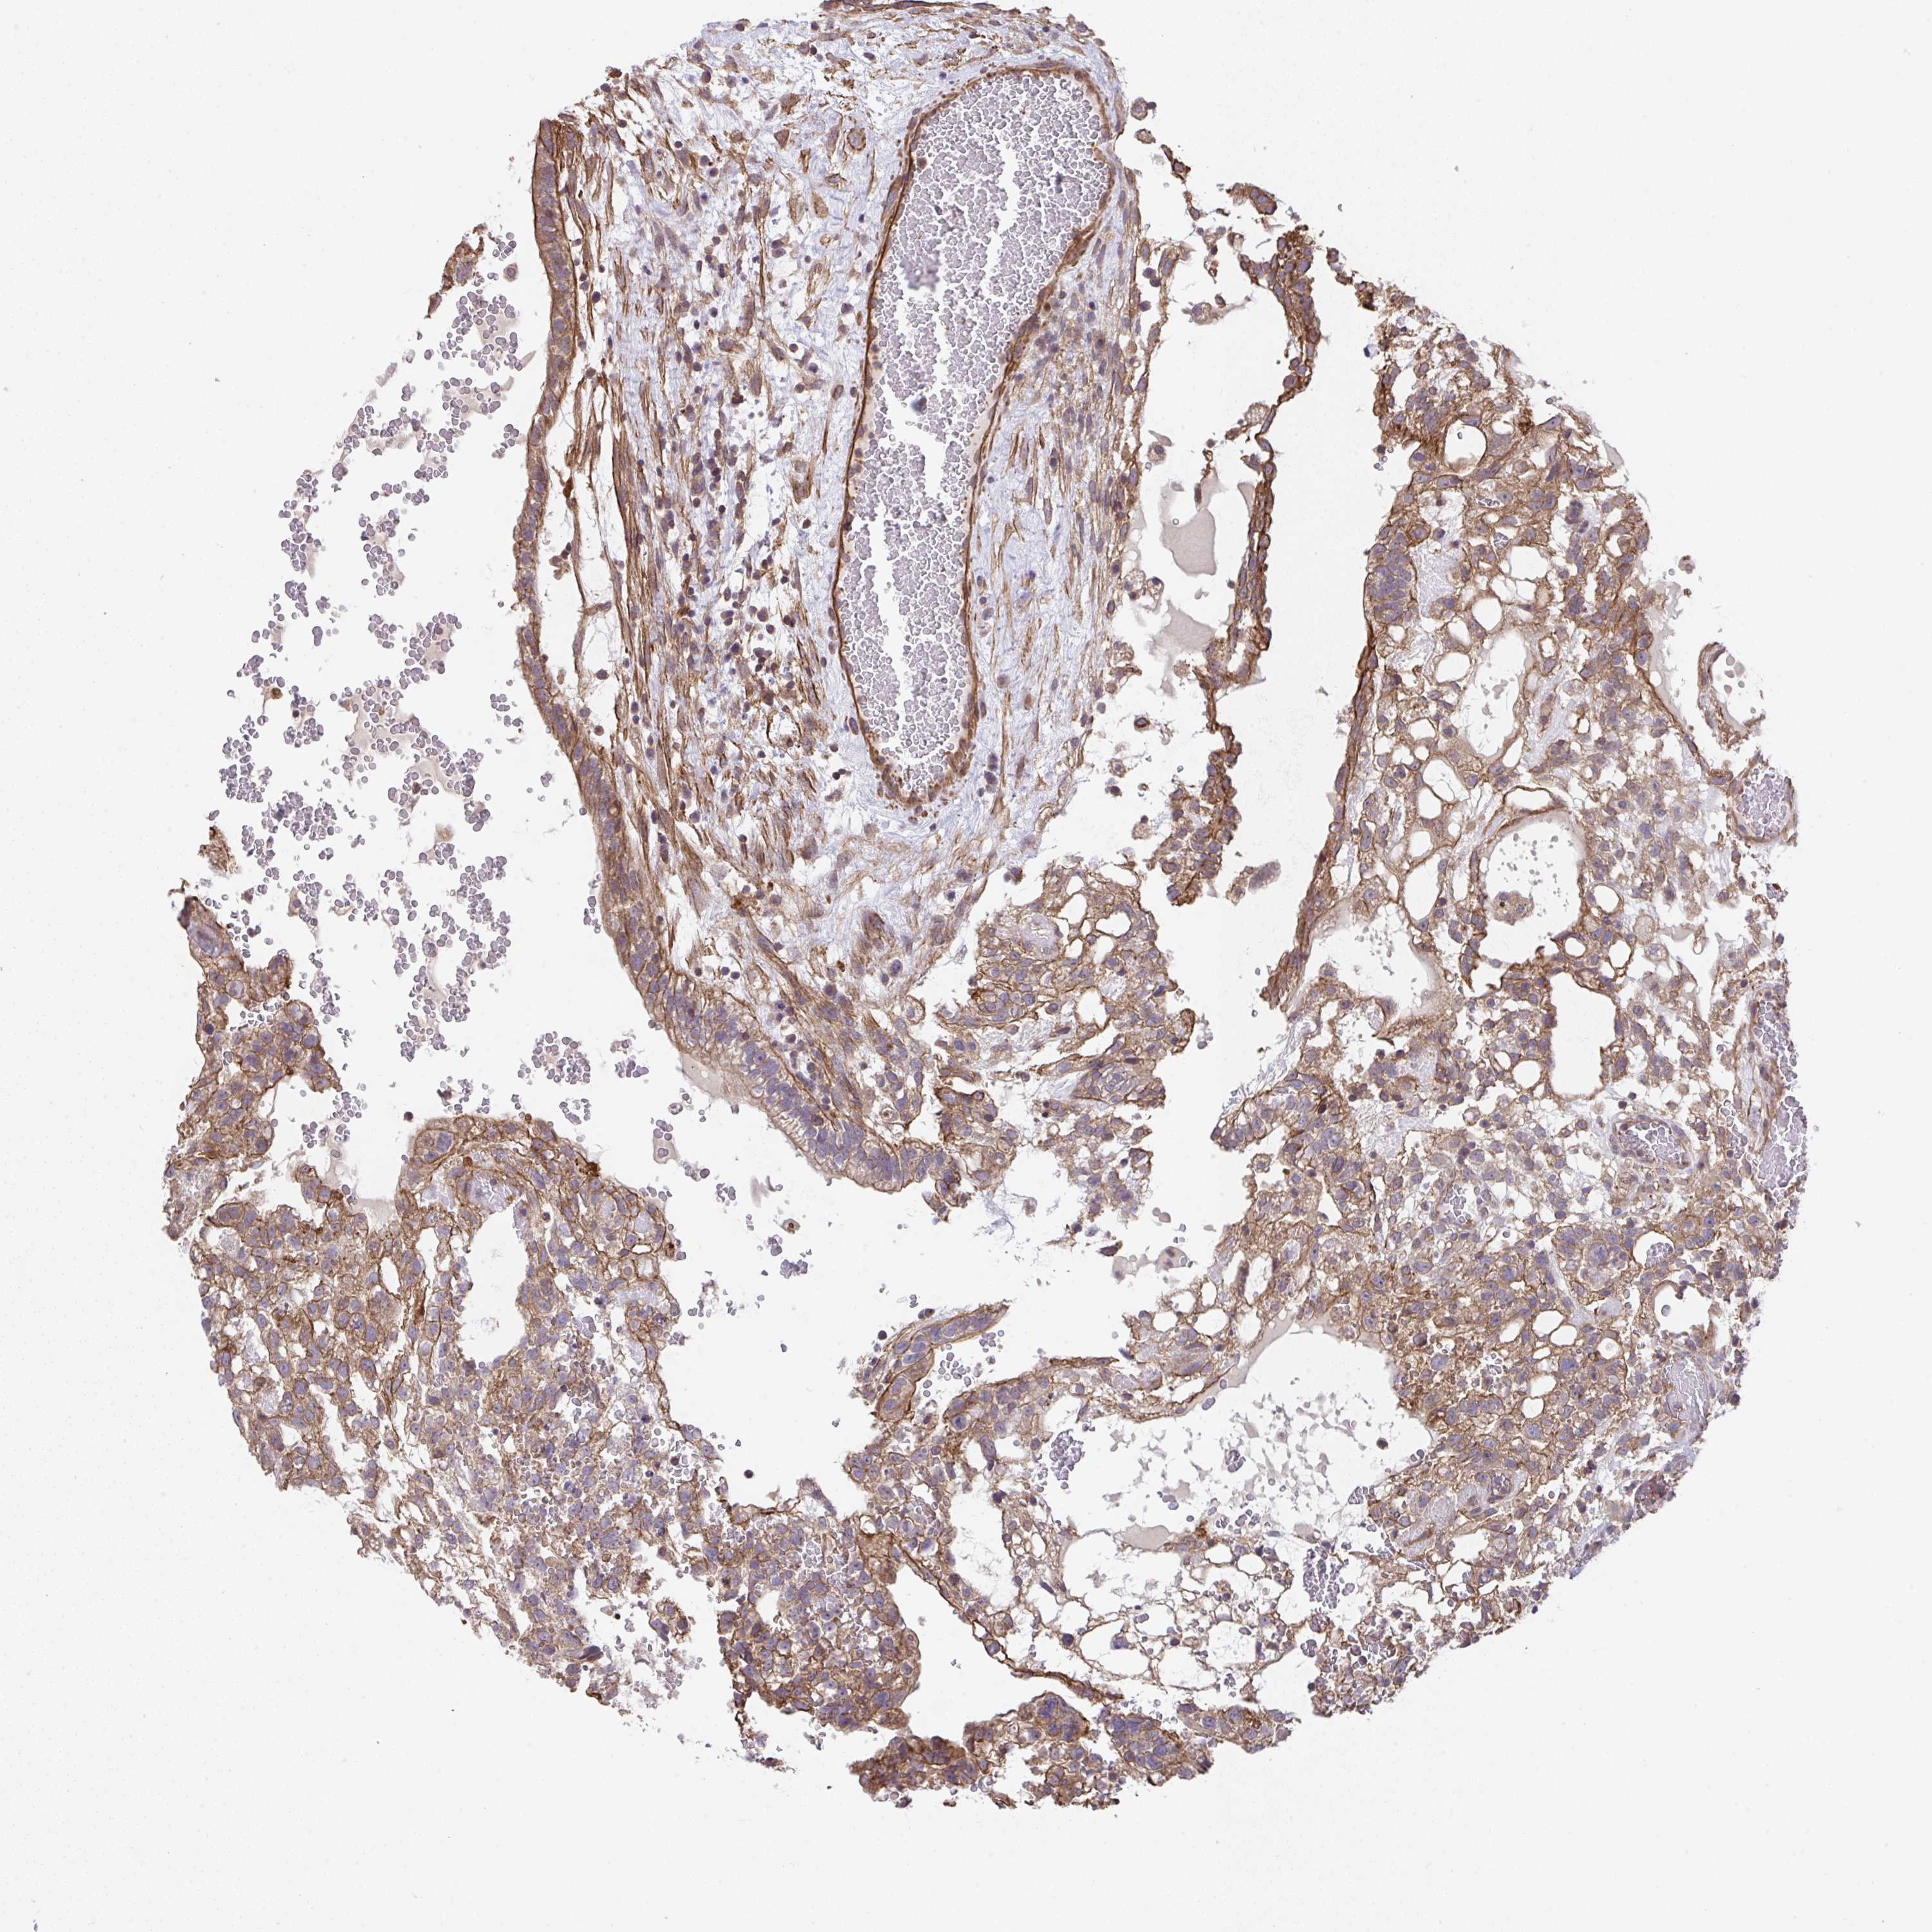

TESTIS CANCER - Protein expressioni

A mouse-over function shows sample information and annotation data. Click on an image to view it in a full screen mode. Samples can be filtered based on level of antibody staining by selecting one or several of the following categories: high, medium, low and not detected. The assay and annotation is described here.

Note that samples used for immunohistochemistry by the Human Protein Atlas do not correspond to samples in the TCGA dataset.

Antibody stainingi

Antibody staining in the annotated cell types in the current human tissue is reported as not detected, low, medium, or high, based on conventional immunohistochemistry profiling in selected tissues. This score is based on the combination of the staining intensity and fraction of stained cells.

Each image is clickable and will lead to virtual microscopy that enables deeper exploration of all samples and also displays staining intensity scores, fraction scores and subcellular localization as well as patient and tissue information for each sample.

Antibody HPA057855

Staining

High

Medium

Low

Not detected

Intensity

Strong

Moderate

Weak

Negative

Quantity

>75%

75%-25%

<25%

None

Location

Nuclear

Cytoplasmic/membranous

Cytoplasmic/membranous,nuclear

Teratoma, malignant, NOS